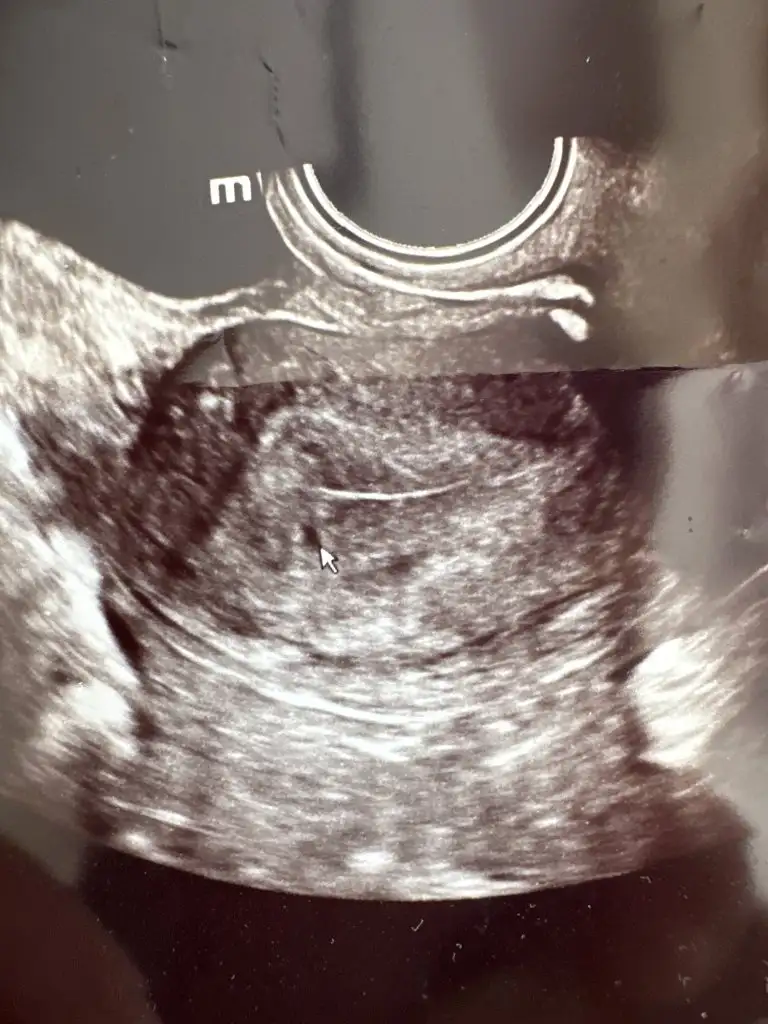

Merhabalar benim de 5 + 4 günlük gebelik dün doktora gittim yolk ile ilgili bir şey demedi görünmüyor sanki dedi anlamadım bende. Zaten şu an erken dedi görünmesi için dedi. İki hafta sonra gel dedi. Çok merak ediyorum atsam yorumlar mı herkes

Arkadasin paylaştığı gibi kesin vardir hatta isaret aldigi kisimda gri uzunlamasina gozukuyor senin de